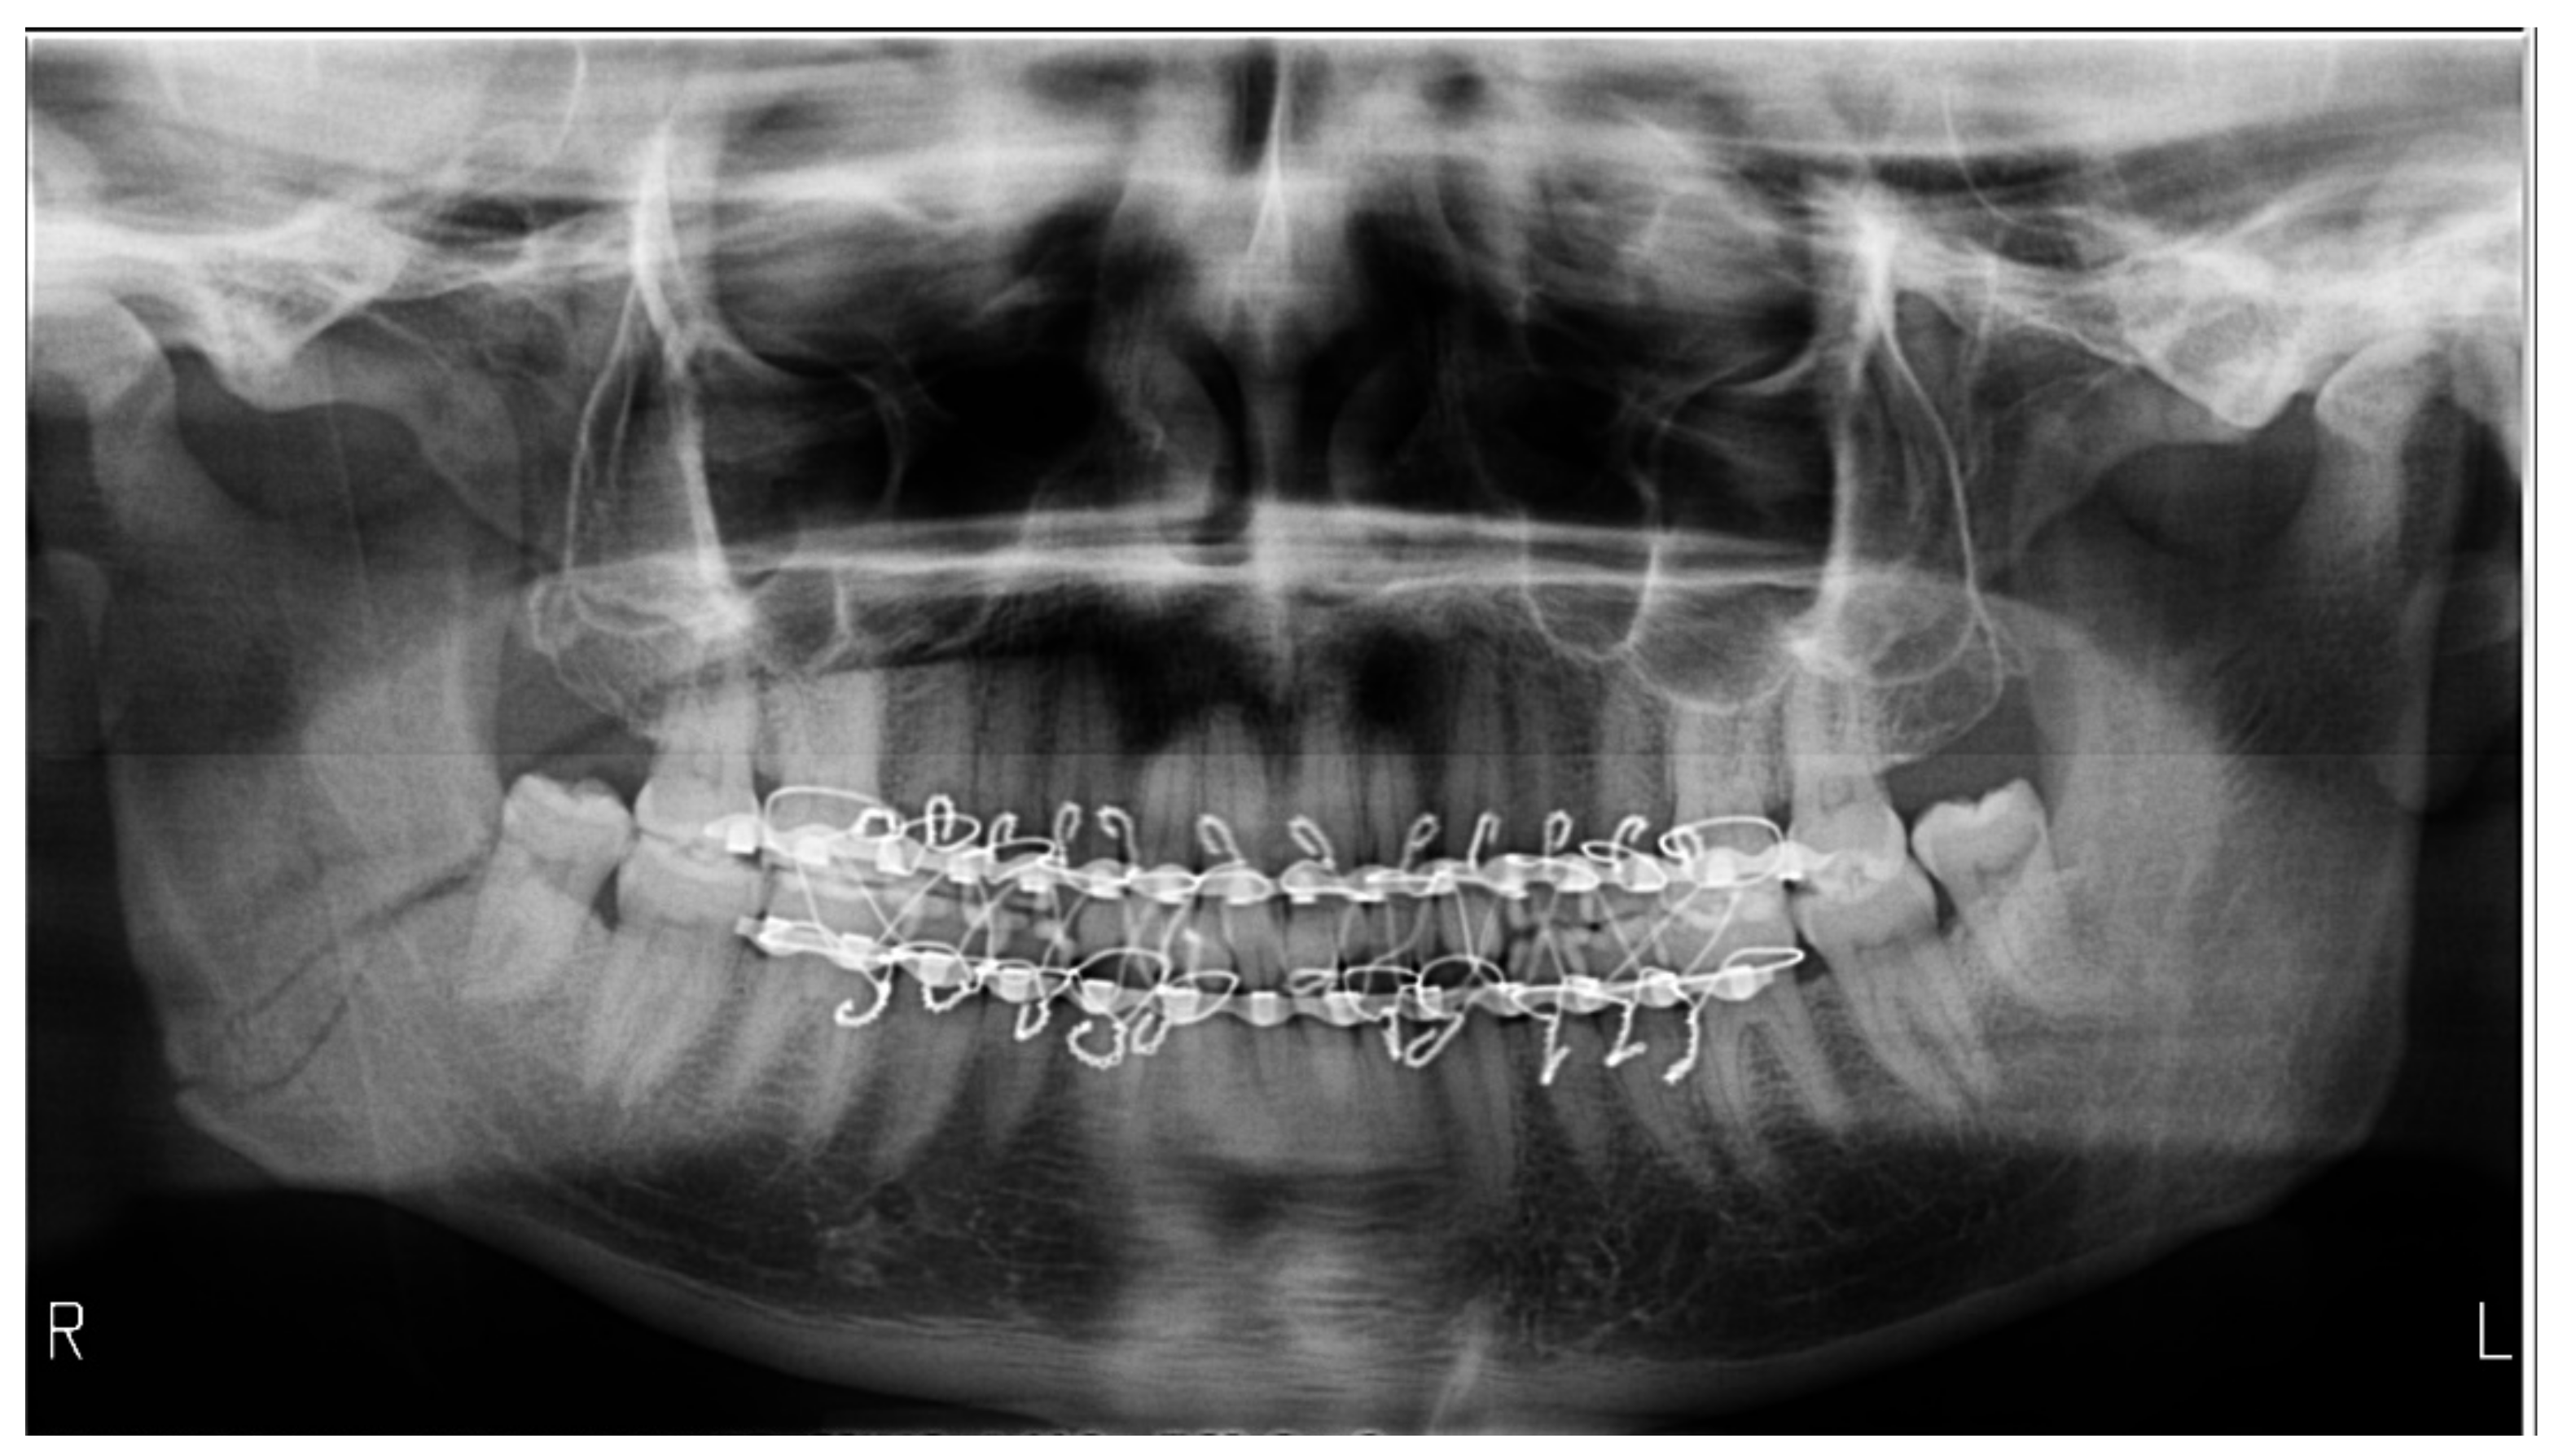

| Absence of bite-block | 28 | 93.33 | 51.85 | [78.68–98.15] |

| Radiographs with bimaxillary immobilization errors | 23 | 76.66 | 62.16 | [59.07–88.21] * |